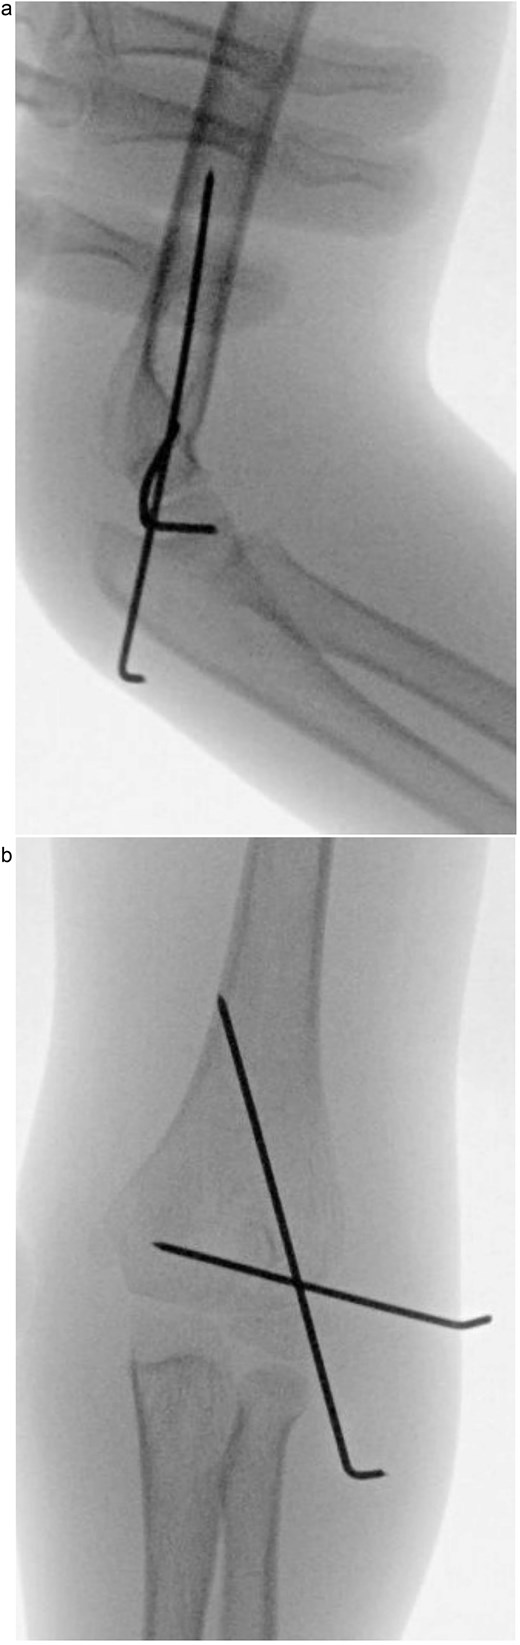

Under procedural sedation, closed reduction of the elbow dislocation was performed, restoring joint alignment and stability. However, post-reduction imaging showed persistent displacement of the lateral condyle fragment (Fig. 2a). The patient was subsequently taken to the operating room, where closed reduction of the condylar fracture was carried out under general anesthesia. As post-reduction displacement was less than 2–4 mm with intact articular cartilage, fixation was performed using two smooth Kirschner wires under fluoroscopic guidance. An arthrogram confirmed joint congruity and cartilage integrity (Fig. 3a). A long-arm posterior slab was applied with the elbow in <90° of flexion to minimize the risk of compartment syndrome (Fig. 4a).

(a) Postoperative anteroposterior radiograph demonstrating stable fixation of the lateral condyle with two smooth Kirschner wires. (b) Lateral view showing proper wire placement and a well-aligned elbow maintained in a posterior slab splint.